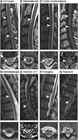

1. 脊髄梗塞の診断にはMRIが推奨される(推奨度1)